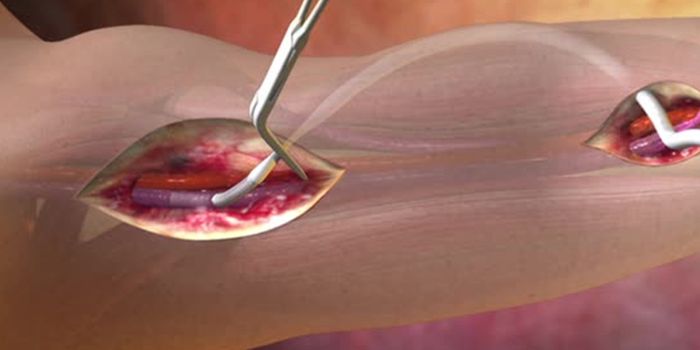

JUN 22, 2017CardiologyDissolving clots deep in the veins has never been easier, thanks to new technology stemming from a collaboration between ...

MAR 19, 2015CardiologyA technique used to clear blood clots from arteries to the heart in about 20 percent of patients undergoing angioplasty ...